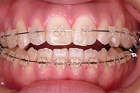

☆審美ワイヤー(光拡散型)の使用例と

ホワイトワイヤー(コーティング)での治療例

審美ホワイトワイヤー

光拡散ロジウムコートtypeワイヤー

ゴールドシリーズ審美ワイヤー

ホワイトコーティングtypeワイヤー